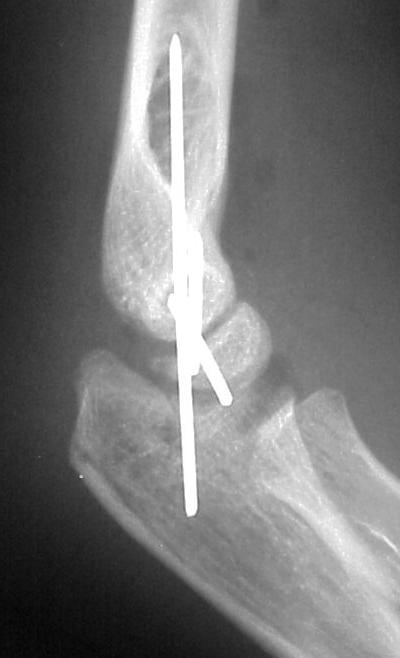

Open reduction and fixation:

Click for larger image